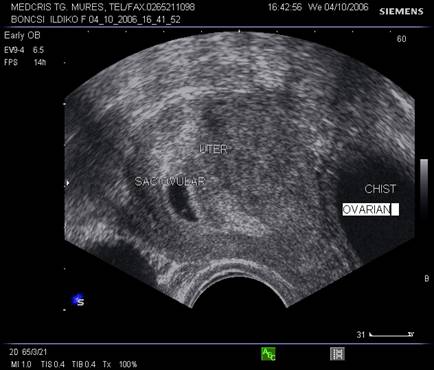

Fig. nr. 9 Sarcina de 5 saptamani la ecografia abdominala.( sacul ovular marcat cu o sageata ) Se remarca retrouterin o formatiune anecogena de peste 5 cm ( chist ovarian marcat cu doua sageti )

Fig. nr. 96. Aceeasi sarcina ca in figura precedenta, retrouterin chist ovarian evident la ecografia transvaginala